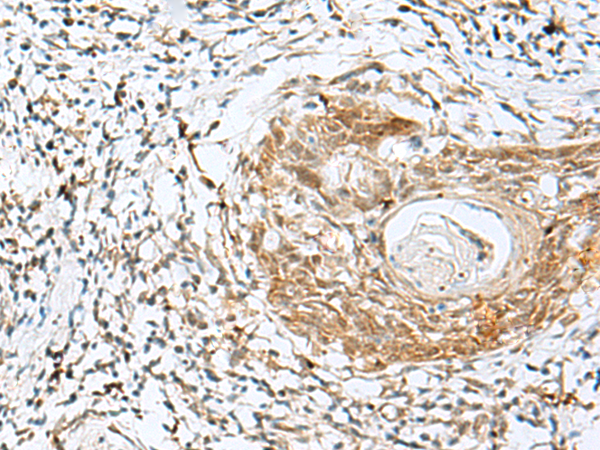

分类: 科研抗体货号: P09849别名: SRCRB4D; S4D-SRCRB; SRCRB-S4D应用: IHC反应种属: Human